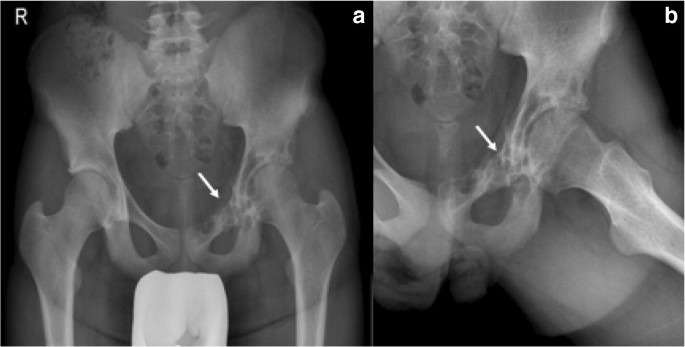

Imaging Features And Floating Ice Sign Of Primary Lymphoma Of The Bone Iranian Journal Of Radiology Full Text

Primary bone lymphoma (pbl) is a subtype of lymphoma that exclusively affects skeletal tissue.

Primary bone lymphoma is an extremely rare condition in which a lymphoma starts in the bones. Primary bone lymphoma is an extremely rare condition in which a lymphoma starts in the bones. Radiation therapy can be used as an adjuvant in some cases. Primary lymphoma of bone (plb) is a rare type of cancer that starts in the bone instead of the lymph nodes.